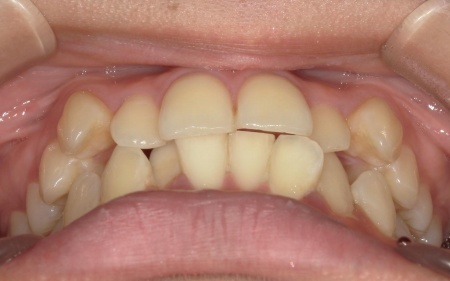

20代女性 八重歯と歯並びの乱れをマウスピース矯正装置で改善した症例

「上下の八重歯が気になる」とご相談いただきました。

拝見したところ、歯が正しく並ぶためのスペースが不足しており、歯が重なって生えてしまう叢生(そうせい)の状態が全体的に見られました。

特に上下の糸切り歯が外側にずれている、いわゆる八重歯が目立っています。

患者様の場合は上下あごの位置関係から噛み合わせに大きな問題はなく、横顔のバランスや鼻先とあごを結んだEラインにも目立った乱れは見られませんでした。